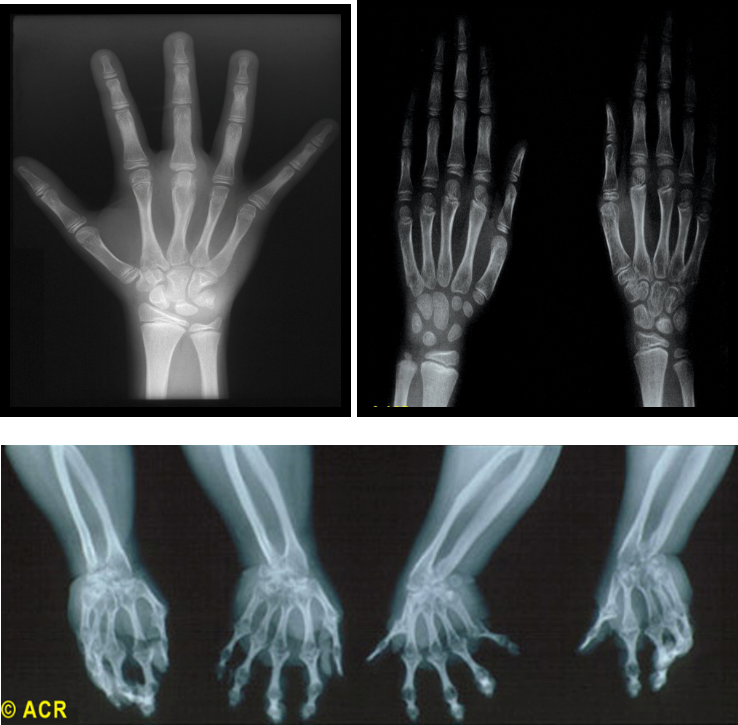

X 线

X线和MRI